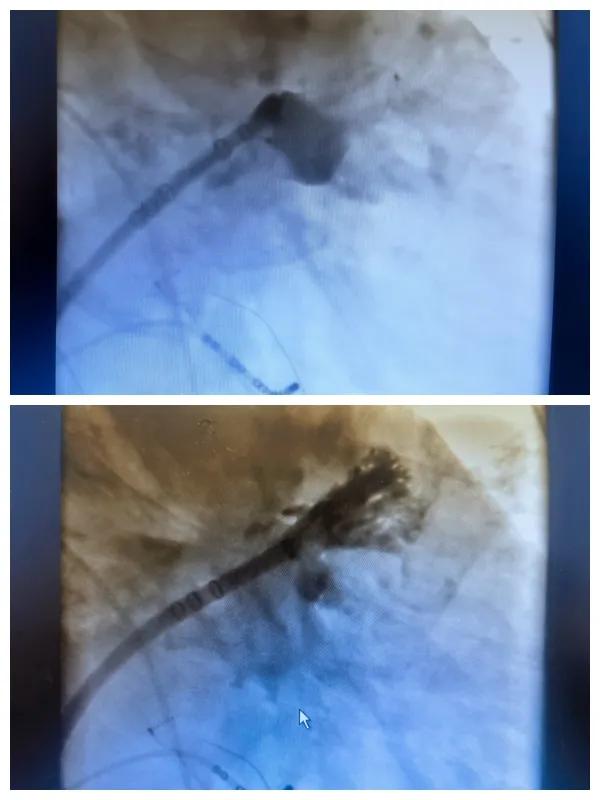

6月26日,市二院成功為一名老年房顫患者實(shí)施了房顫射頻消融術(shù)+左心耳封堵WM FLX一站式介入治療,標(biāo)志著醫(yī)院在心律失常介入治療領(lǐng)域邁出了嶄新的一步,開啟了新的治療篇章。

為了讓患者得到全面、綜合的治療,經(jīng)過團(tuán)隊(duì)術(shù)前充分討論,并征得家屬同意,心血管內(nèi)科團(tuán)隊(duì)決定采用目前國(guó)內(nèi)外先進(jìn)的房顫射頻消融術(shù)+左心耳封堵WM FLX一站式介入微創(chuàng)手術(shù)來治療老人的疾病。整個(gè)手術(shù)過程圓滿順利,術(shù)后何大爺各項(xiàng)體征正常,蘇醒后順利返回病房。

針對(duì)一部分栓塞風(fēng)險(xiǎn)高的病人,但是病人又存在有抗凝藥禁忌的情況下,如何在解決房顫的同時(shí)又預(yù)防栓塞的發(fā)生?一站式手術(shù)應(yīng)運(yùn)而生,通過導(dǎo)管消融將其轉(zhuǎn)成竇性心律,解決或減少病人心衰發(fā)生,另外通過左心耳封堵術(shù),代替終身口服抗凝藥來進(jìn)一步預(yù)防栓塞事件的發(fā)生。